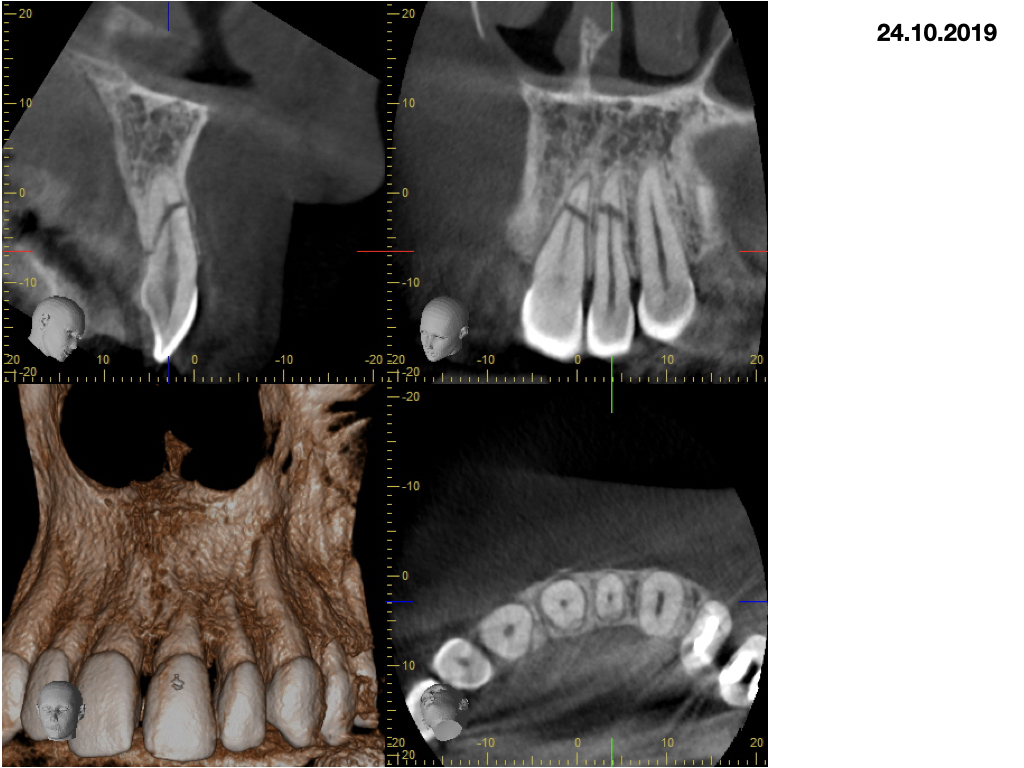

Wurzelfrakturen